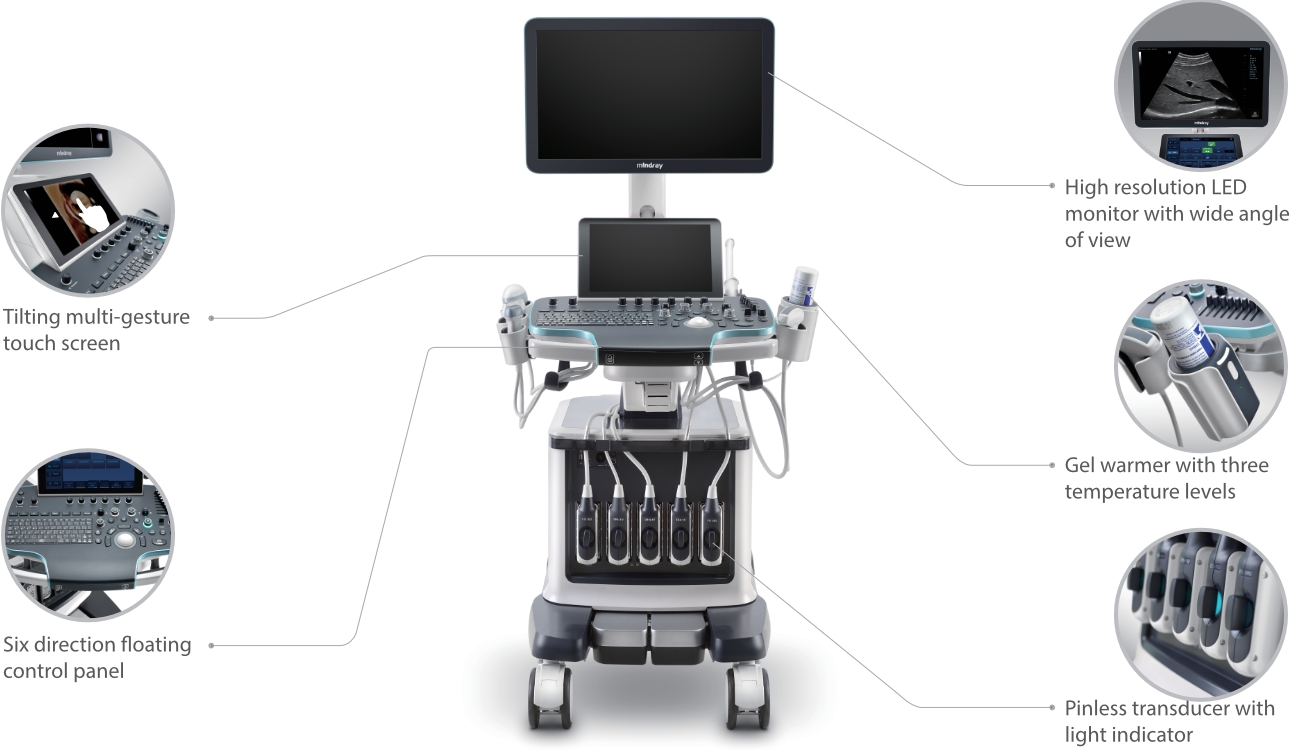

Resona 7

Nuevas ondas en la innovaciÃģn de ultrasonido

Desde su creaciÃģn, Mindray no ha dejado de explorar nuevas maneras de mejorar la fiabilidad del diagnÃģstico. Gracias a ZONE Sonography?, la tecnologÃa mÃĄs revolucionaria, la nueva plataforma ZST+ del Resona 7 eleva la calidad de imagen de ultrasonido mediante la adquisiciÃģn de zonas y el procesamiento de datos de canal.

AdemÃĄs de una calidad superior de la imagen, el Resona 7 tambiÃĐn mejora las capacidades de investigaciÃģn clÃnica gracias al revolucionario V Flow para la evaluaciÃģn hemodinÃĄmica vascular y la adquisiciÃģn de planos mÃĄs inteligente a partir de un conjunto de datos 3D para el diagnÃģstico CNS fetal. Combinando el funcionamiento multitÃĄctil mÃĄs intuitivo basado en gestos y todas las funciones clÃnicas esenciales, el Resona 7 estÃĄ realmente encabezando nuevas ondas en la innovaciÃģn del campo del ultrasonido.